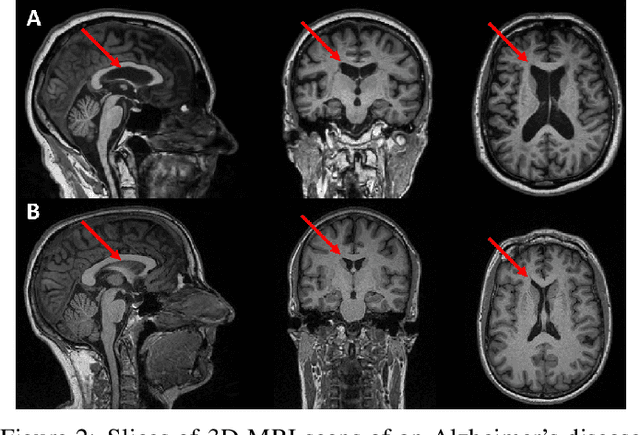

Abstract:For precision medicine and personalized treatment, we need to identify predictive markers of disease. We focus on Alzheimer's disease (AD), where magnetic resonance imaging scans provide information about the disease status. By combining imaging with genome sequencing, we aim at identifying rare genetic markers associated with quantitative traits predicted from convolutional neural networks (CNNs), which traditionally have been derived manually by experts. Kernel-based tests are a powerful tool for associating sets of genetic variants, but how to optimally model rare genetic variants is still an open research question. We propose a generalized set of kernels that incorporate prior information from various annotations and multi-omics data. In the analysis of data from the Alzheimer's Disease Neuroimaging Initiative (ADNI), we evaluate whether (i) CNNs yield precise and reliable brain traits, and (ii) the novel kernel-based tests can help to identify loci associated with AD. The results indicate that CNNs provide a fast, scalable and precise tool to derive quantitative AD traits and that new kernels integrating domain knowledge can yield higher power in association tests of very rare variants.